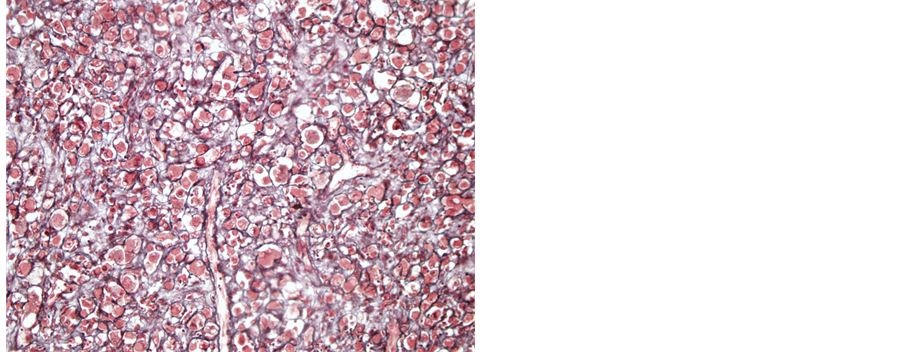

A 32-year-old male patient presented with a generalized epileptic seizure. Neurological examination was normal. Cerebral computerized tomography (CT) and magnetic resonance imaging (MRI) revealed a small solid lesion localized at the frontal lobe, without clear dural attachment, inhomogeneously hyperdense/hyperintense, with irregular enhancement after contrast injection (Figure 1). The patient underwent operation with a preoperative diagnosis of high grade glioma. Histopathologically a dense hypercellular glial tumor was observed. Histopathological and immunohistochemical features (Figure 2 and Figure 3) are summarized in Table 1. A diagnosis of APXA was given. Six months later control MRI revealed a recurrent mass lesion. The morphologic features of the recurrent tumor were similar with that of the primary tumor except for that necrosis was present in the recurrent tumor. Histopathological and immunohistochemical features (Figure 4) are summarized in Table 2. Recurrent tumor was also diagnosed as APXA. In both tumors BRAF V600E mutation was detected by FISH method. p16 mutation was not observed.

Figure 3. GFAP immunopositivity in tumoral cells (Case 1― primary tumor; GFAP, 100×).